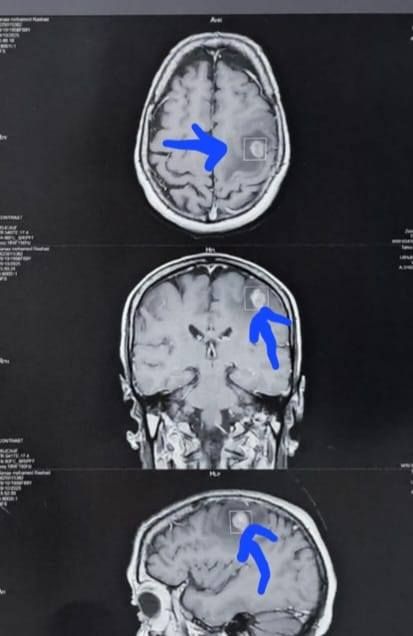

وكشف الدكتور إبراهيم الغريب رئيس قسم جراحة المخ والأعصاب بالمستشفى، أنه تعود تفاصيل الحالة إلى استقبال المستشفى المريضة بالعيادة الخارجية وهي تشكو من تنميل وضعف بالجانب الأيمن وثقل بسيط في الكلام، وبإجراء الفحوصات اللازمة من أشعة مقطعية ورنين مغناطيسي بالصبغة، تبين وجود ورم بالمخ، وتم إعطاؤها العلاج المناسب لحين استكمال الفحوصات.

أشعة المريضة

الأشعة الخاصة بالمريضة

الأشعة